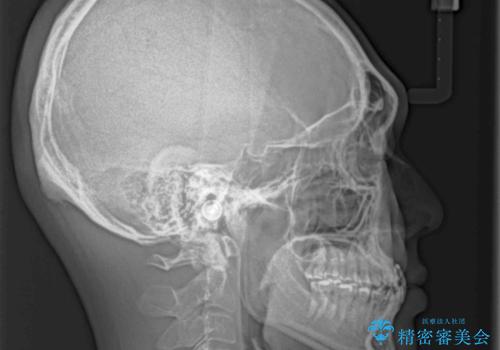

前歯のクロスバイトを改善 ワイヤー装置での非抜歯矯正

- 骨格的な咬み合わせのズレ、前歯のデコボコとクロスバイトを気にして来院された患者様です。

骨格のズレが顕著であると診断され、マウスピース矯正では奥歯の咬み合わせが整えにくいと判断し、ワイヤー装置による矯正治療を行うこととしました。

上下の叢生は速やかに改善できましたが、右側のクロスバイトの改善に1年以上の期間を要しました。